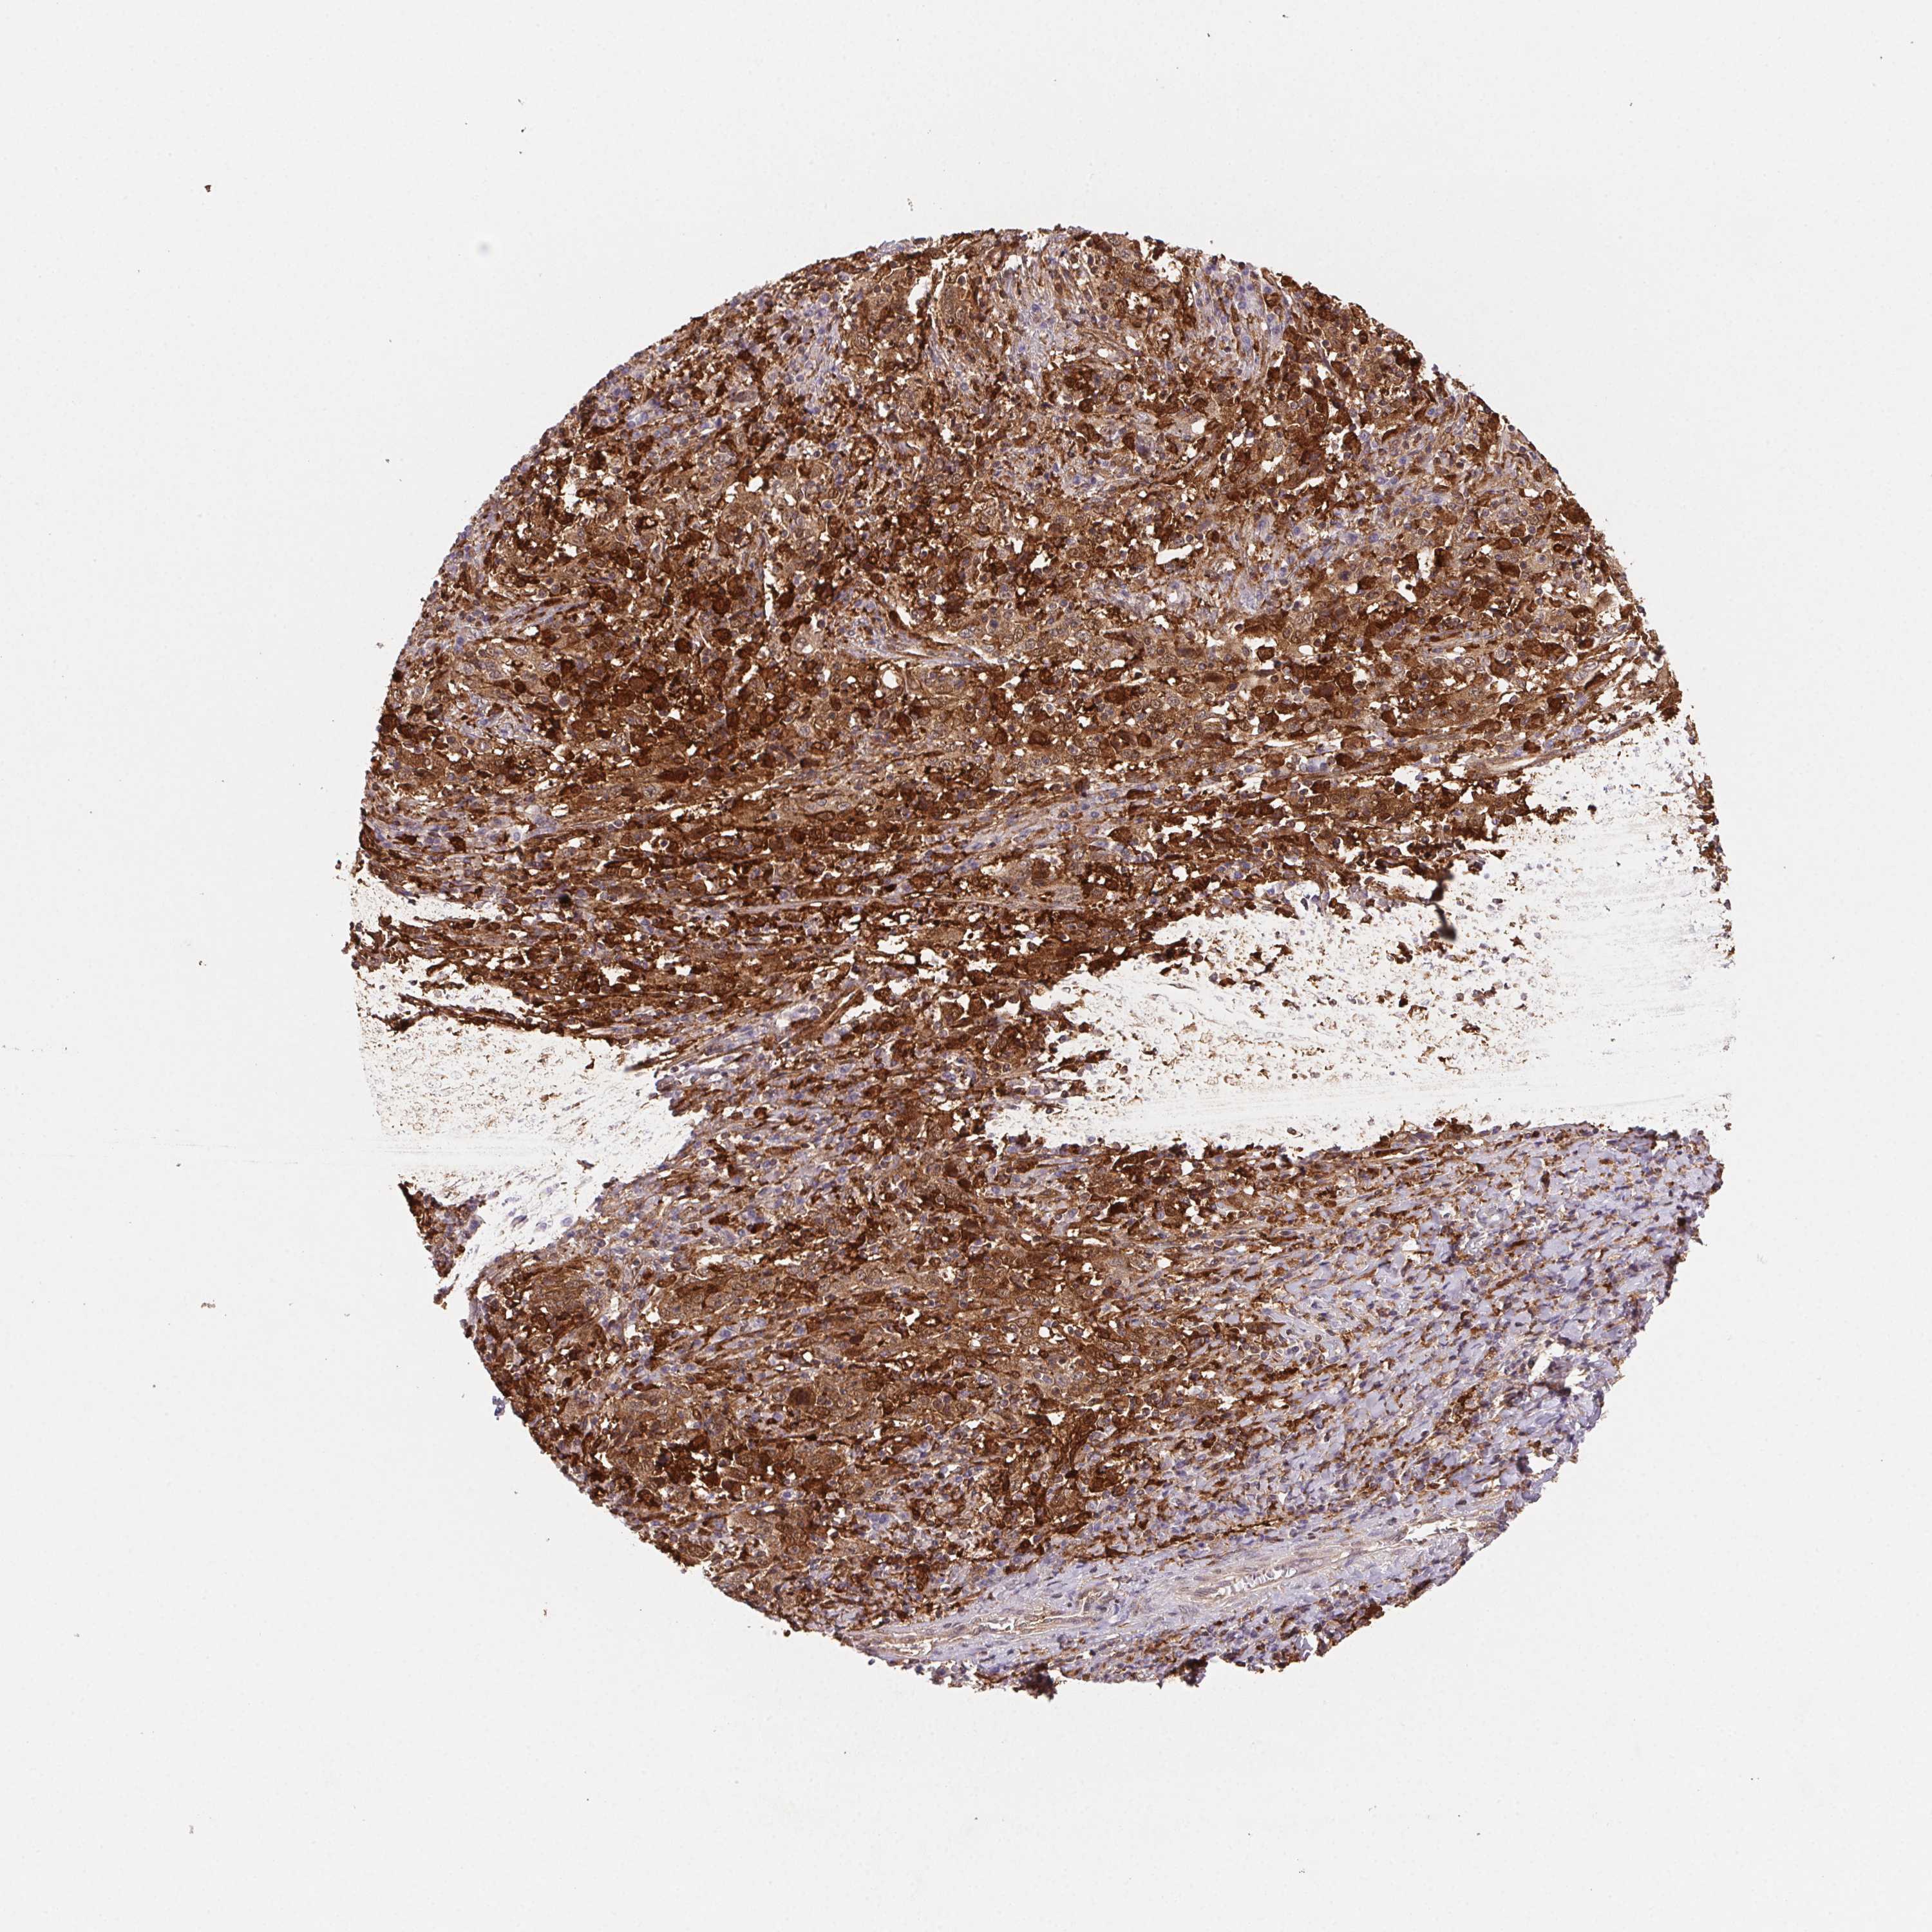

CERVICAL CANCER - Protein expressioni

A mouse-over function shows sample information and annotation data. Click on an image to view it in a full screen mode. Samples can be filtered based on level of antibody staining by selecting one or several of the following categories: high, medium, low and not detected. The assay and annotation is described here.

Note that samples used for immunohistochemistry by the Human Protein Atlas do not correspond to samples in the TCGA dataset.

Antibody stainingi

Antibody staining in the annotated cell types in the current human tissue is reported as not detected, low, medium, or high, based on conventional immunohistochemistry profiling in selected tissues. This score is based on the combination of the staining intensity and fraction of stained cells.

Each image is clickable and will lead to virtual microscopy that enables deeper exploration of all samples and also displays staining intensity scores, fraction scores and subcellular localization as well as patient and tissue information for each sample.

Antibody CAB015450

Staining

High

Medium

Low

Not detected

Intensity

Strong

Moderate

Weak

Negative

Quantity

>75%

75%-25%

<25%

None

Location

Nuclear

Cytoplasmic/membranous

Cytoplasmic/membranous,nuclear

Squamous cell carcinoma, NOS